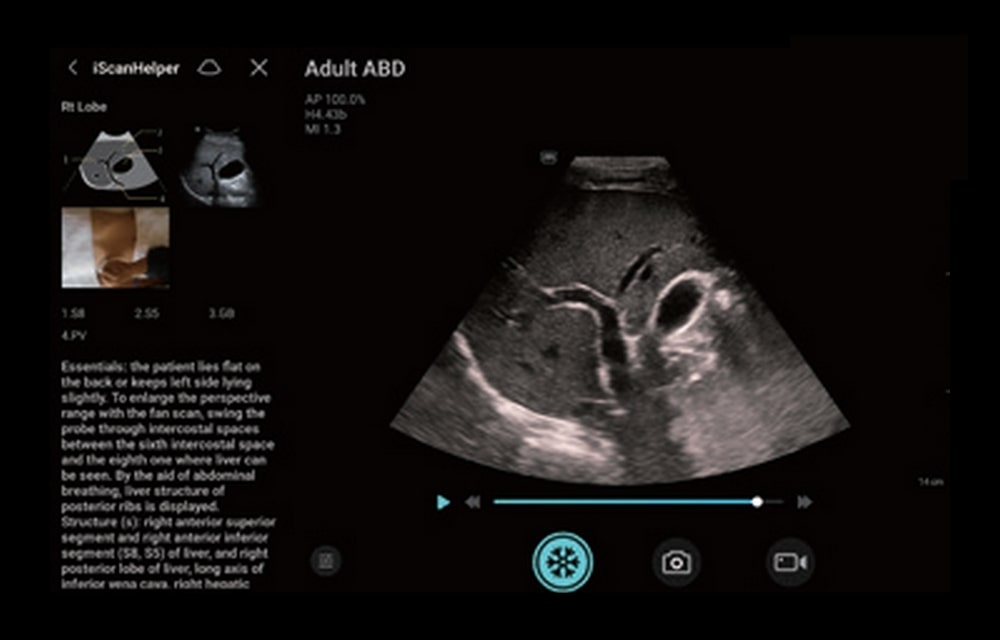

L’ecografo palmare TE Air, rappresenta oggi il Top tra gli ecografi portatili. Il trasduttore collegato ad uno smartphone o ad un tablet in modalità Wifi, garantisce prestazioni full body di qualità superiore alla media degli ecografi ultraportatili. Consente l’uso, in emergenza, di applicazioni diverse.

TE Air grazie alle sue dimensioni ed al peso ridotto è perfetto per uso mobile ed a domicilio del paziente. L’ecografo palmare è molto semplice nel suo utilizzo e pronto all’uso in pochi secondi. La durata della batteria interna garantisce un’autonomia di lavoro superiore all’ora e mezza ed il tempo di ricarica è di soli trentacinque minuti. Facile da pulire, con superficie resistente ai disinfettanti per un impiego igienico. TE Air e5M è in grado di gestire la scansione dell’intero corpo e di adattarsi a vari scenari clinici. Il suo design wireless consente esami ecografici di alta qualità in qualsiasi momento e ovunque. Oltre alla sua versatilità, TE Air e5M offre anche una gamma di funzioni intelligenti e strumenti didattici per aumentare la sicurezza e l’efficienza.